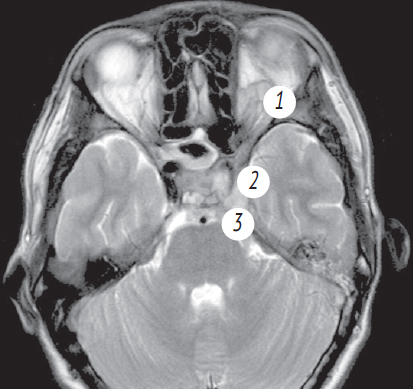

24.11.2021 выполнено МРТ головного мозга: отмечается улучшение пневматизации правых отделов пазухи клиновидной кости, левая верхнечелюстная пазуха полностью пневматизирована. Отмечается увеличение просвета сифона левой внутренней сонной артерии, отсутствие отека ретробульбарной клетчатки левого глаза, уменьшение объема тромба левого кавернозного синуса (рис. 7).

Рис. 7. Магниторезонансная томография головного мозга от 24.11.2021: а — аксиальная проекция в режиме Т1. Пневматизация пазухи клиновидной кости практически полностью восстановлена; b — коронарная проекция в режиме Т1. Сифоны внутренних сонных артерий имеют одинаковый просвет; c — аксиальная проекция в режиме Т2. Улучшение пневматизации правой основной пазухи; d — аксиальная проекция в режиме Т2. Отсутствие экзофтальма левого глаза, купирован отек ретробульбарной клетчатки слева. Увеличение просвета сифона внутренней сонной артерии слева; e — коронарная проекция в режиме Т2. Пневматизация верхнечелюстной пазухи слева полностью восстановлена

Fig. 7. Magnetic resonance imaging of the head from 24.11.2021: a – axial projection in T1 mode. Pneumatization of the sphenoid sinus is almost completely restored; b – coronal projection in T1 mode. Siphons of the internal carotid arteries have the same lumen; c – axial projection in T2 mode. Improvement of pneumatization of the right main sinus; d – axial projection in T2 mode. The absence of exophthalmos of the left eye, edema of the retrobulbar tissue on the left was stopped. Increase in the lumen of the siphon of the internal carotid artery on the left; e – coronal projection in T2 mode. Pneumatization of the maxillary sinus on the left was completely restored